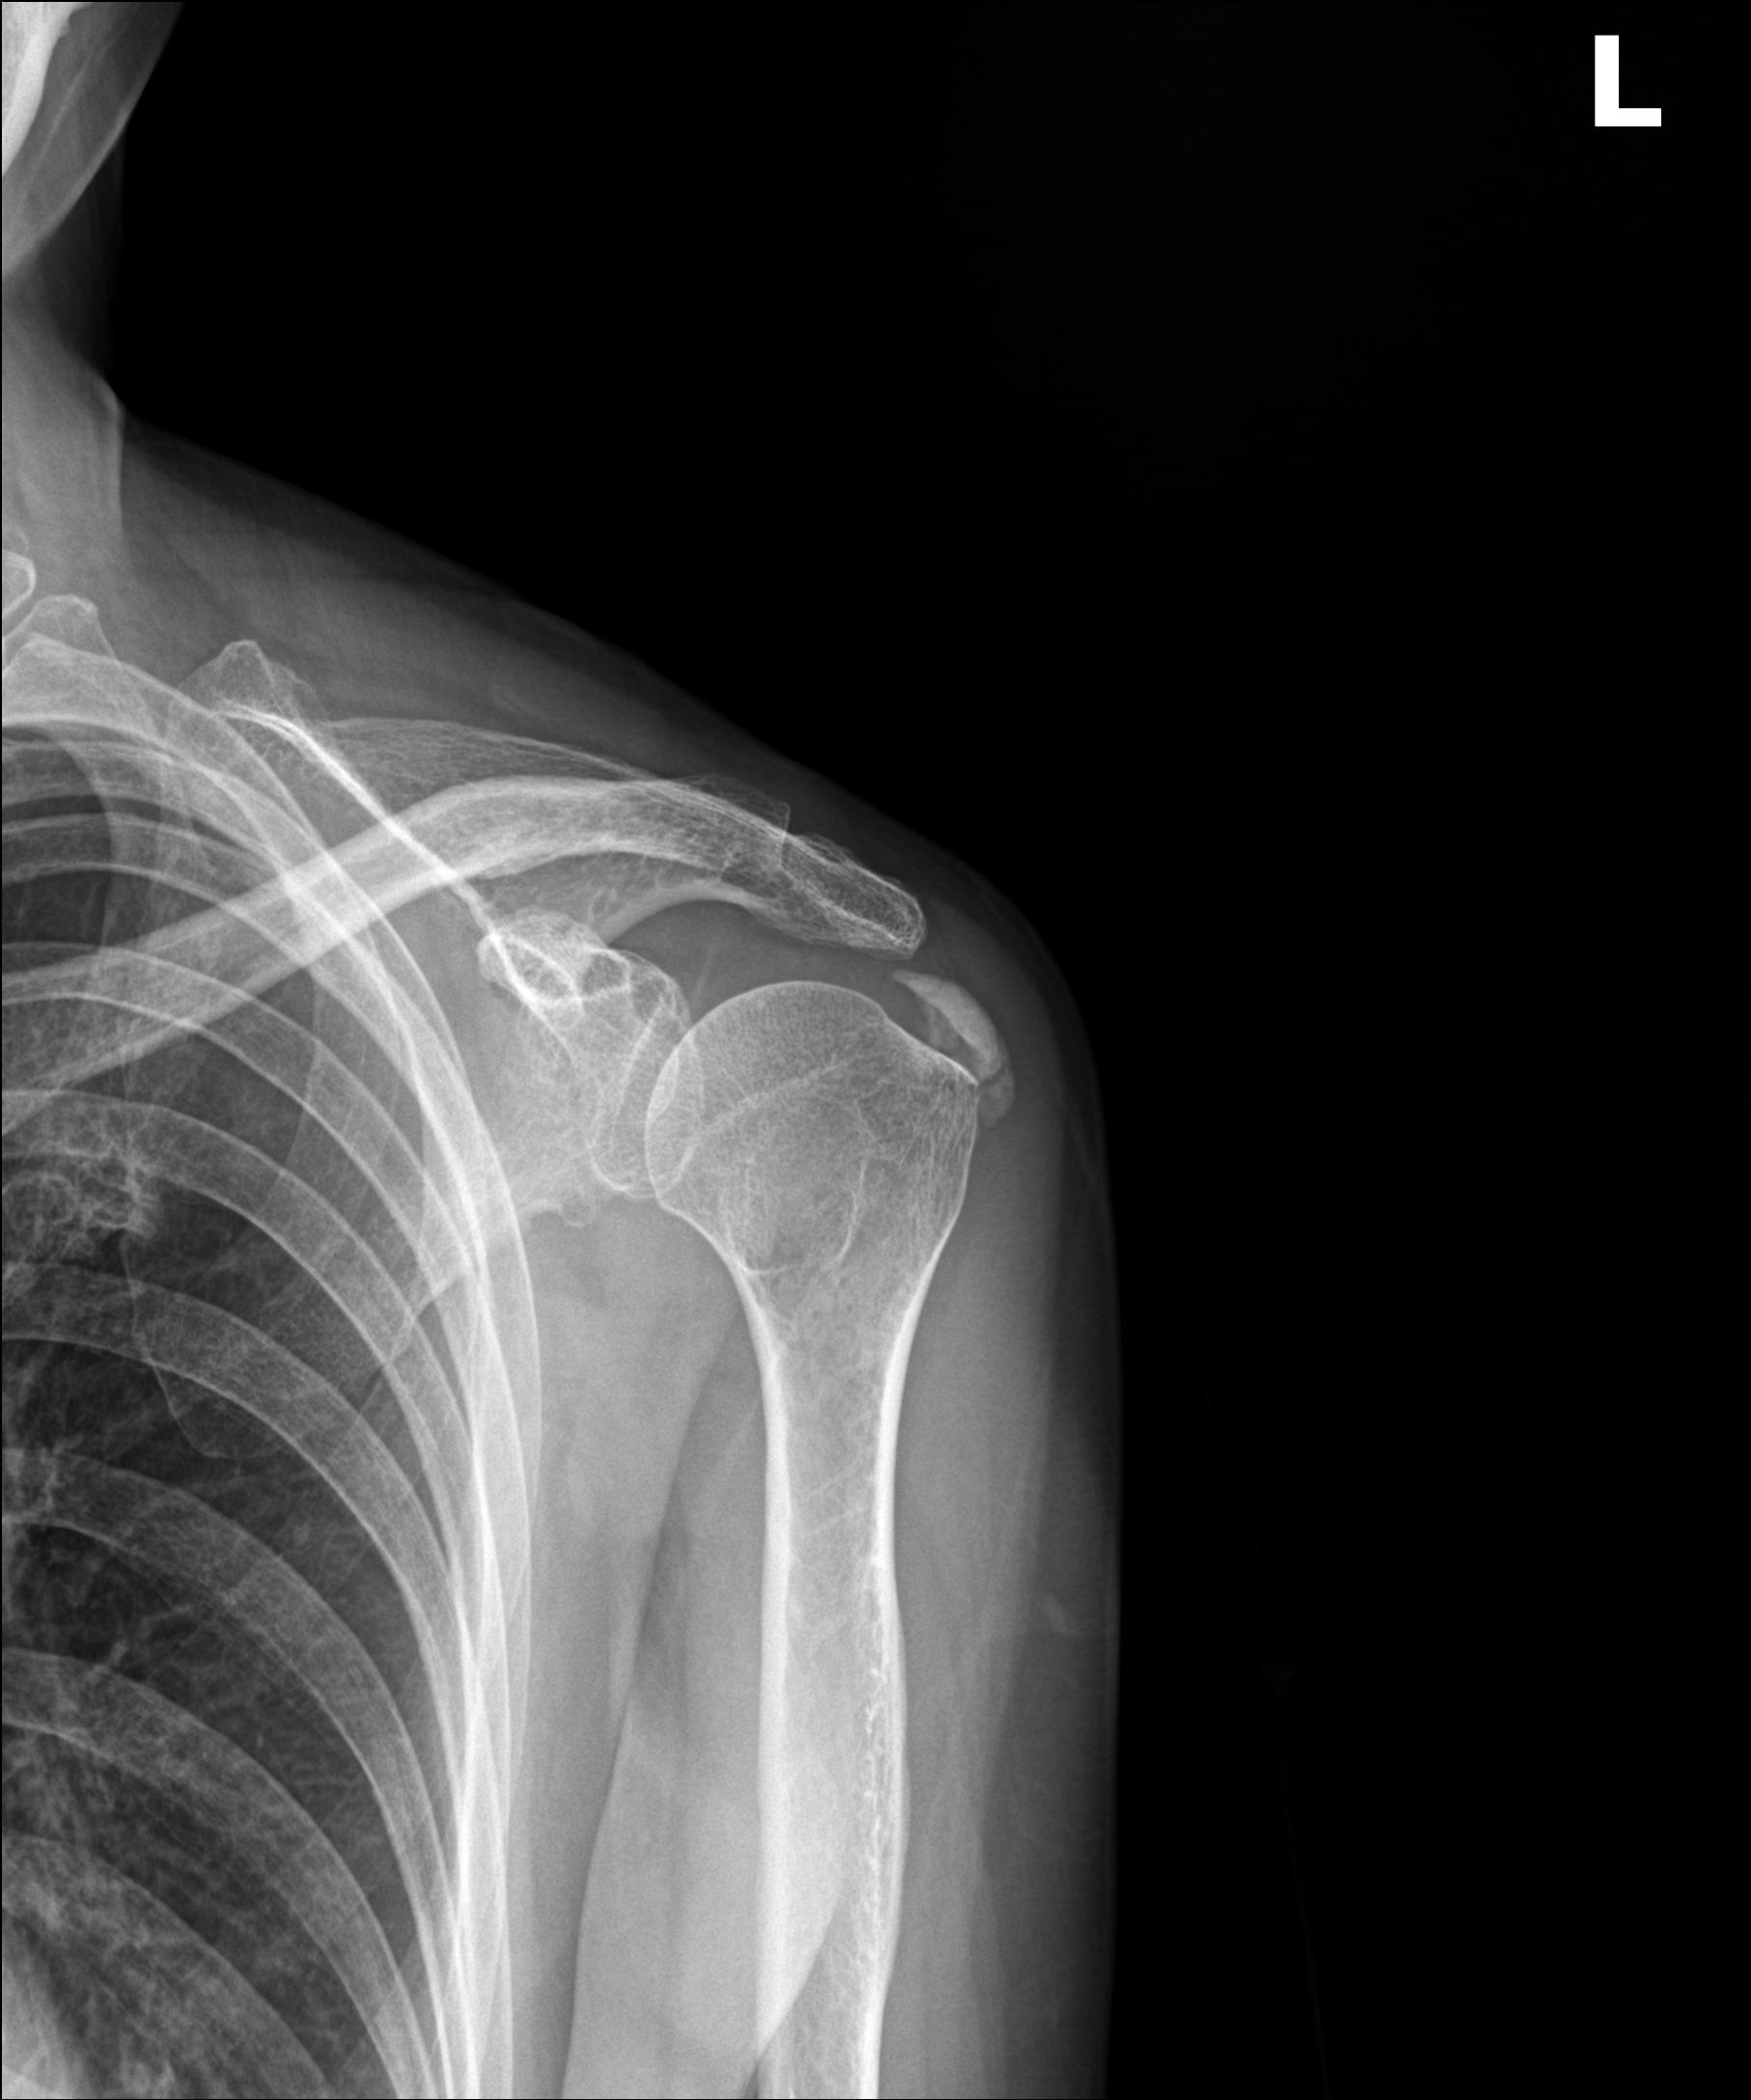

X-ray 검사: 뼈와 석회를 봅니다

- ✓뼈의 골절 여부

- ✓골극(뼈가 가시처럼 자라난 것) 유무

- ✓석회 침착 여부 (석회성건염 진단)

- ✓관절 간격 (관절염 진행 정도)

Q2. X-ray만으로 회전근개 파열을 진단할 수 있나요?

A. 없습니다. X-ray는 뼈를 보는 검사이므로, 인대 파열은 확인할 수 없습니다.

Q3. 석회성건염은 어떤 검사로 진단하나요?

A. X-ray만으로도 진단이 가능합니다.